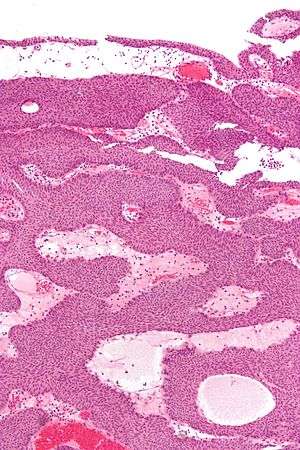

| Micrograph of an inverted papilloma of the urinary bladder. H&E stain. | |

Histopathology representing an inverted papilloma of the urinary bladder that was cystoscopically resected. Hematoxylin and eosion stain.